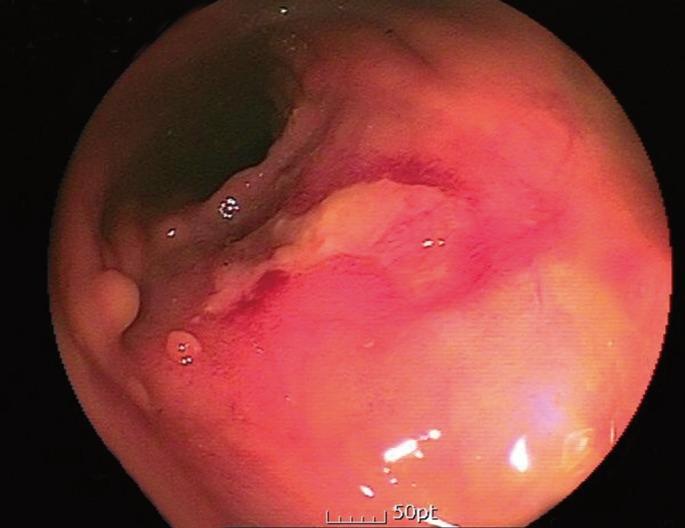

Necrotizing fasciitis usually occurs after dermal injury or through hematogenous spread. To date, few cases have been reported as necrotizing fasciitis of the thigh secondary to rectal perforation in rectal cancer patients. A 66-year-old male complained of pelvic and thigh pain and subsequently developed necrotizing fasciitis in his right thigh. Four years earlier, he had undergone a low anterior resection and radiotherapy due to of rectal cancer. An ulcerative lesion had been observed around the anastomosis site during the colonoscopy that had been performed two months earlier. Pelvic computed tomography and sigmoidoscopy showed rectal perforation and presacral abscess extending to buttock and the right posterior thigh fascia. Thus, the necrotizing fasciitis was believed to have occurred because of ulcer perforation, one of the complications of chronic radiation colitis, at the anastomosis site. When a rectal-cancer patient complains of pelvic and thigh pain, the possibility of a rectal perforation should be considered.

坏死性筋膜炎通常发生在皮肤损伤后或通过血行播散。迄今为止,很少有病例报道为直肠癌患者因直肠穿孔继发大腿坏死性筋膜炎。一名66岁男性主诉盆腔和大腿疼痛,随后右大腿发生坏死性筋膜炎。四年前,他因直肠癌接受了低位前切除术和放疗。在两个月前进行的结肠镜检查中,吻合口周围观察到溃疡性病变。盆腔计算机断层扫描和乙状结肠镜检查显示直肠穿孔和骶前脓肿延伸至臀部和右后大腿筋膜。因此,坏死性筋膜炎被认为是由于慢性放射性结肠炎的并发症之一——吻合口溃疡穿孔所致。当直肠癌患者主诉盆腔和大腿疼痛时,应考虑直肠穿孔的可能性。